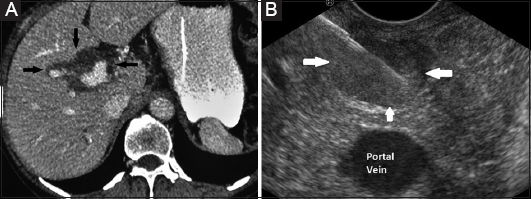

Abdomen And Retroperitoneum 1 1 Liver Case 1 1 11 Fatty Liver And Focal Sparing Ultrasound Sonography Diagnostic Medical Sonography Ultrasound